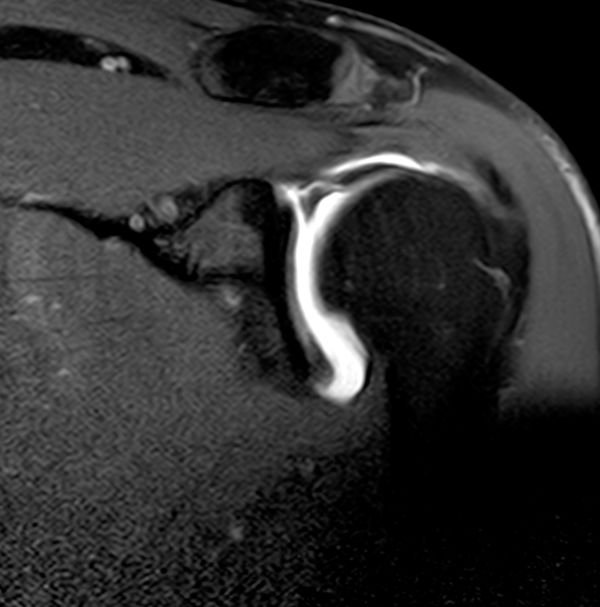

MRA is recognised as the gold standard for SLAP diagnosis. Multiple studies showed high sensitivities and specificities in SLAP lesion diagnosis: sensitivity ranges from 82% to 100%, specificity is between 71% and 98%, accuracy varies between 83% and 94% [29][16]. Intra-articular contrast has reported to be useful to exclude anatomic variants.[13]

Images in the axial and coronal oblique planes are most useful for the SLAP lesions evaluation. The fibrocartilaginous labrum most often has a triangular structure, but it may change shape dynamically with traction from the capsule or glenohumeral ligaments (e.g., appear round or flattened). Regardless, if there is no high signal either at the labral–chondral junction or through the labrum, the labrum should be graded as normal. The sublabral sulcus (also referred to as a sublabral recess) and sublabral foramen are frequent anatomic variations, in which a segment of the labrum is not attached to the underlying glenoid. Typically a sublabral sulcus appears as a cleft of smooth, medially curved increased signal at the chondrolabral junction that does not extend posterior to the biceps anchor. The depth of the recess is variable, but typically less than 2 mm. Despite that, it must be emphasized that high signal of more than 3 mm on MRA extending anterior and posterior to the biceps anchor or laterally in the substance of the tendon is the hallmark of SLAP lesions (Figure 10).[14]

SLAP Lesion

Figure 10. MRA coronal view of a SLAP lesion with T1 SPIR 3 sequences. Full-thickness detachment with laterally curved high signal intensity and wide separation (width >3 mm on MRA) between the labrum and glenoid. Reproduced from XX with permission.